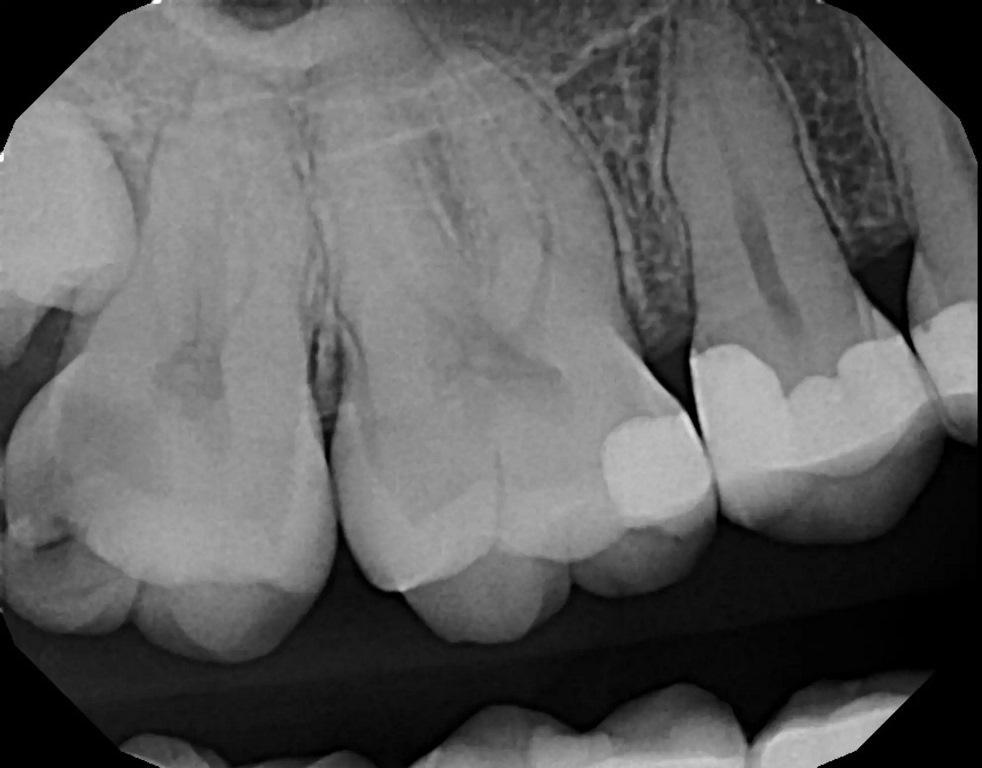

57-летний пациент обратился с жалобами на повышенную чувствительность к температуре в левом квадранте верхней челюсти. Был сделан рентгеновский снимок (фото 2), на котором был отмечен глубокий кариес на втором премоляре с возможным вовлечением пульпы. Периапикальная патология рентгенологически не была отмечена. Чтобы убедиться в жизнеспособности пульпы зуб подвергли испытанию холодом (фриз-тест). При проведении фриз-теста была отмечена слабая реакция, которая немедленно прошла, когда холод был удален с зуба, что указывало на то, что зуб был жизненно важным. Пациенту сообщили, что может потребоваться эндодонтическое лечение, если в результате удаления кариеса произойдет значительное обнажение пульпы или у зуба появятся симптомы после лечения. Если обнаруживается небольшое обнажение пульпы или в результате удаления кариеса дентин над пульпой становится тонким, перед установкой культевой вкладки следует провести лазерную обработку, чтобы стерилизовать область и избежать развития пульпита. Для этого зуба планировалось установить культевую вкладку и полную коронку. Пациент принял рекомендации по лечению.

Фото 2: Периапикальная рентгенограмма зуба №25, на которой виден кариес в непосредственной близости от пульпарной ткани.